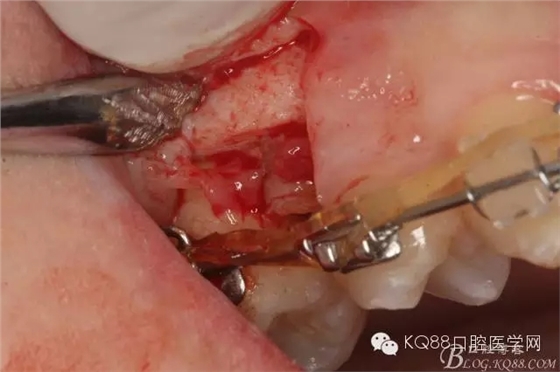

圖8.因16與14合面的間隙僅2mm左右,牙根無法合向脫位,如何考慮15牙根的脫位將是最大問題。高速手機去除牙間隙內(nèi)的覆蓋在15牙根表面的牙齦組織

圖10.去除牙齦組織后。露出15牙根斷面,合面無法脫位